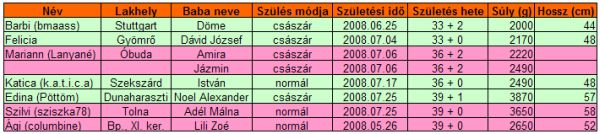

Végre van kis időm bejelentkezni. Köszönjük szépen a gratulációkat és a jókívánságokat, nagyon-nagyon kedvesek vagytok, olyan jól esett! Tényleg!

És én is gratulálok Pöttömnek és Sziszkának is, jó egészséget Nekik!! Olyan jó lesz mostmár, szépen lassan mindenkinek megszületik a kis babája!

Gyorsan rakok fel pár képet, mert azután mennem kell szopiztatni.

Íme a képek: